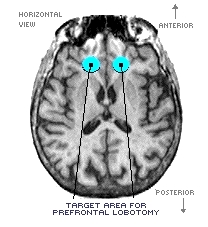

Lobotomy/Psycho-surgery. From the late-1930s to the mid-1950s, physicians performed prefrontal lobotomies, an operation in which the surgeon would cut some of the nerve tracts between the prefrontal tissue and the rest of the brain. It was believed that this would "calm" individuals with severe mental disorders (especially schizophrenia) without impairing motor skills or sensory capacities.

The technique was developed in Europe, but pioneered in the U.S. by a physician, Dr. Walter Freeman, It was used with about 40,000 patients. The operation did not usually result in any significant help to the patient. We know today, for example, that the frontal lobes of schizophrenic patients are under-aroused and, thus, the operation harmed an area that was already functioning poorly.